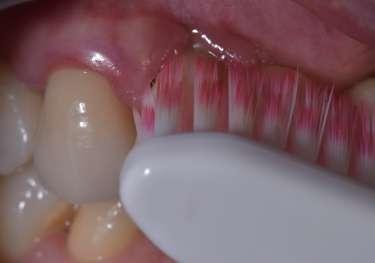

Le innovazioni tecnologiche per l’efficace mantenimento delle riabilitazioni implantari

La prevenzione terziaria è una vera sfida per l’igienista dentale, che per competenza del suo profilo professionale ha la gestione del mantenimento delle riabilitazioni odontoiatriche.

Le terapie riabilitative implantari per pazienti con edentulia parziale o totale, permettono di riportare sia la funzionalità che l’estetica, con una prevedibilità di successo che dipende, oltre che dall’efficace piano terapeutico chirurgico implantare del professionista chirurgo, anche dalla responsabilità attiva del paziente a seguire corretti stili di vita di igiene orale domiciliare e follow-up. Questi devono prevedere la visita diagnostica di controllo dell’implantologo e la visita di controllo dell’igienista dentale. Per sollecitare l’aderence ai follow-up, usare l'automazione workflow e moduli di anamnesi personalizzati (gestionale Alfa Docs) permette una migliore gestione e un monitoraggio efficace delle cure e dei richiami personalizzati in base ai bisogni extra clinici dei pazienti. La vera sfida è il management di igiene orale in pazienti presi in carico che sono stati sottoposti a terapie implantari in altri studi, e che mostrano clinicamente mucosite, con interessamento della mucosa perimplantare o con perimplantite che coinvolge l’osso di sostegno.

Spesso si evidenzia il collare implantare degli abutment, e prima che l’implantologo preveda intervento mucogengivale è fondamentale condividere con il paziente la necessità di eliminare l’infiammazione eseguendo un'igiene orale domiciliare attenta ed efficace. L'igiene orale domiciliare deve essere considerata terapia.

biofilm batterico domiciliare. Per il controllo meccanico del biofilm batterico, se viene lamentata dolorabilità, si deve concordare l'uso di uno spazzolino con setole che siano efficaci ma che non creino dolorabilità durante l’utilizzo (GUM Sonic Sensitive).

L’utilizzo degli scovolini in gomma, (GUM Soft Picks Confort Flex), risultano essere delicati sui tessuti perimplantari, ed efficaci, grazie alle differenti misure possibili, per la personalizzazione della scelta dell’interprossimale a seconda dello spazio sovracrestale.

(TBM) Nardi G.M. et al. Tailored Brushing Method (TBM): an innovative simple protocol to improve the oral care. J Biomed 2016; 1:26-31. Il protocollo di igiene orale deve essere personalizzato in base alla tipologia del manufatto protesico implantare, poiché spesso la persona assistita ha difficoltà di efficacia nel controllo del